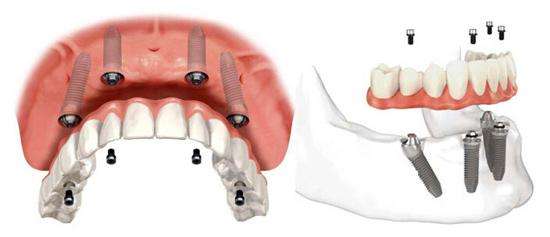

全口种植牙的优势有哪些?随着种植牙技术的不断发展,就目前而言,种植牙几乎可用于各种牙齿缺失以后的修复,例如,单颗、多颗、甚至全口缺牙的患者,都可以通过种植牙进行牙齿修复。种植牙被医学界称为人类的第三颗牙齿,又被称为牙齿缺失患者首选的修复方式。那么,全口种植牙的优势有哪些呢?下面我们一起来看看圣洁口腔专家的详细介绍:

1、恢复咀嚼 :种植牙拥有全固定式的种植体对牙齿进行固位,效果极好,比传统假牙牙套更加的稳固、牢靠,可大幅度的恢复患者咀嚼能力,患者即可尽情地吃、畅快地说、自信地笑。

4、舒适美观:种植牙不需要借助基托与卡环等结构来固位,外观和功能上完全与真牙一样,成功的种植牙口腔内无异物感,有利于保持口腔卫生,舒适美观,使你忘掉假牙的存在。